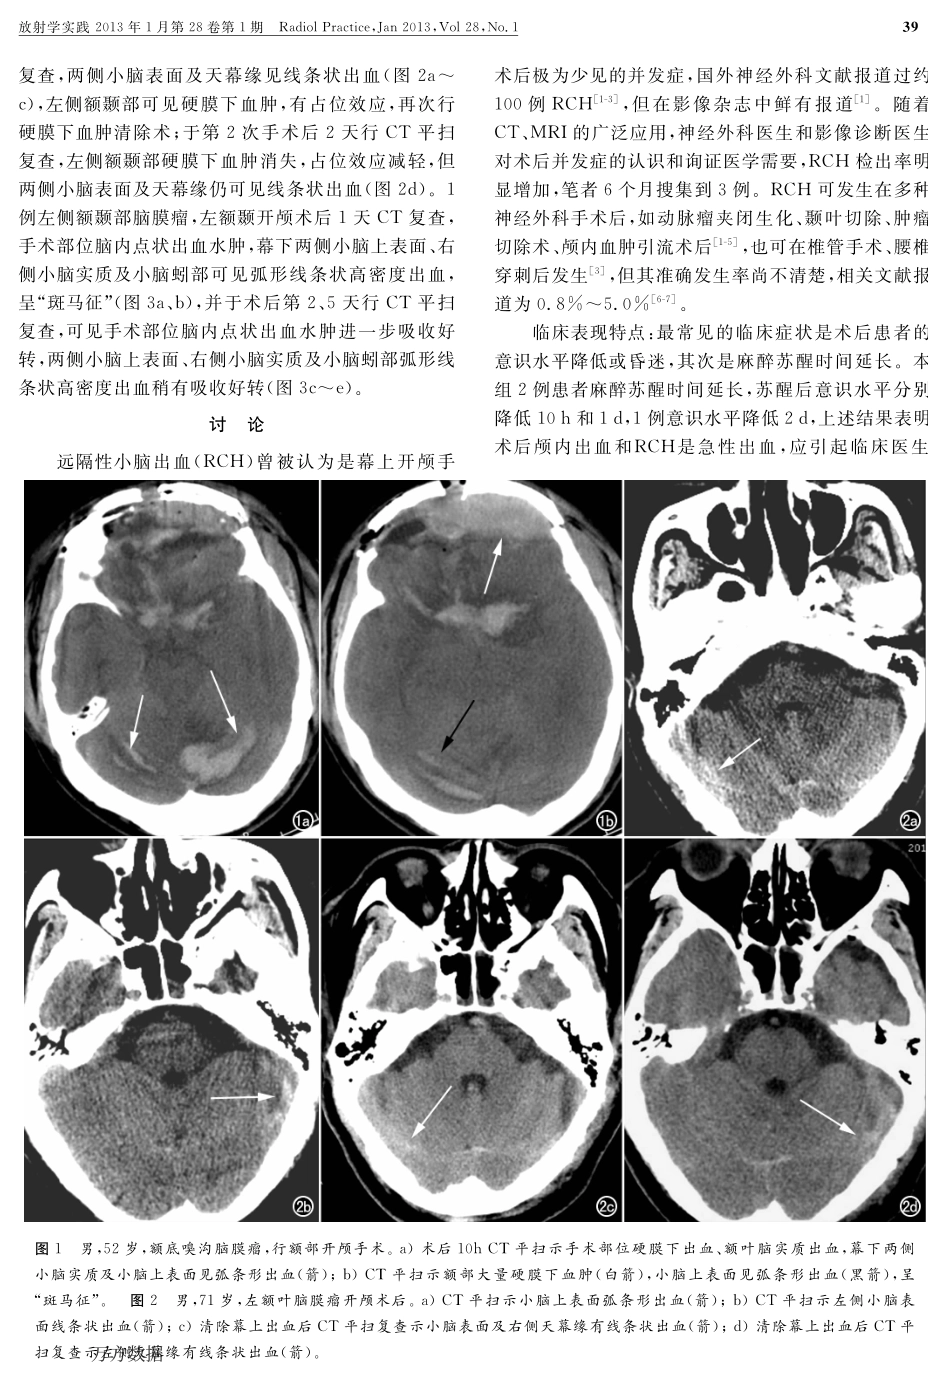

作者单位:437000湖北,咸宁市中心医院/华中科技大学同济咸宁医院影像科(章凯敏、杜希剑);430030武汉,华中科技大学同济医学院附属同济医院放射科(管汉雄、姜琼、周义成);430030武汉,华中科技大学同济医学院附属协和医院PET中心(贾清)作者简介:章凯敏(1978-),女,湖北咸宁人,主治医师,主要从事CT与MRI诊断工作。·中枢神经影像学·远隔性小脑出血CT表现章凯敏,杜希剑,管汉雄,贾清,姜琼,周义成【摘要】目的:探讨幕上开颅术后远隔性小脑出血(RCH)的临床及影像表现。方法:3例脑膜瘤患者行开颅手术后出现意识障碍,行紧急CT平扫发现并发RCH,回顾性分析RCH的临床及影像学表现。结果:2例术后手术部位可见大量硬膜下血肿及少量蛛网膜下腔�血,此2例可见两侧小脑上表面脑沟、脑叶�血,呈“斑马征”;1例手术后可见少量左侧小脑上表面叶及右侧天幕缘出血。结论:典型RCH表现为小脑单侧或双侧表面沟或小脑叶裂弧条线高密度影,呈“斑马征”,为其特征性CT表现,与术后颅内压突然增高或降低,引起脑组织移位,导致桥静脉断裂有关。【关键词】远隔性小脑出血;脑脊液;神经外科手术;体层摄影术,X线计算机【中图分类号】R651.1;R814.42【文献标识码】A【文章编号】10000313(2013)01003804犜犺犲犆犜犿犪狀犻犳犲狊狋犪狋犻狅狀狊犪狀犱犱犻犪犵狀狅狊犻狊狅犳狉犲犿狅狋犲犮犲狉犲犫犲犾犾犪狉犺犲犿狅狉狉犺犪犵犲ZHANGKaimin,DUXijian,GUANHanxiong,etal.DepartmentofMedicalImaging,XianningCentralHospital,Hubei437000,P.R.China【犃犫狊狋狉犪犮狋】犗犫犼犲犮狋犻狏犲:Toinvestigatetheclinicalandimagingmanifestationsofremotecerebellarhemorrhage(RCH)aftersupratentorialcraniotomies.犕犲狋犺狅犱狊:Threepatientsofmeningiomahadunconsciousnessoccurredaftersupratentorialcraniotomy,RCHwasfoundonCTwithoutcontrastenhancementduringemergency.TheclinicalandimagingmanifestationsofRCHwereretrospectivelyanalyzed.犚犲狊狌犾狋狊:Massivesubduralhematomaandasmallamountofsubarachnoidhemorrhagelocatedattheoperationregionwerefoundintwopatients,withbilateralsuperficialcerebellarsulciandlobarhemorrhage,showingas“ZebraSign”.Thethirdpatientpresentedwithsmallamountofhemorrhageintheleftsuperiorsulciandrightinfratentorialregion.犆狅狀犮犾狌狊犻狅狀:ThetypicalCTmanifestationsofRCHappearsashighdensityinunilateralorbilateralsuperficialsulciorcerebellarfissures,whichisreferredas“ZebraSign”.ItisbelievedthatRCHisrelatedtosuddenincreaseordecreaseofintracranialpressure,displacementofbraintissue,whichleadstolacerati...